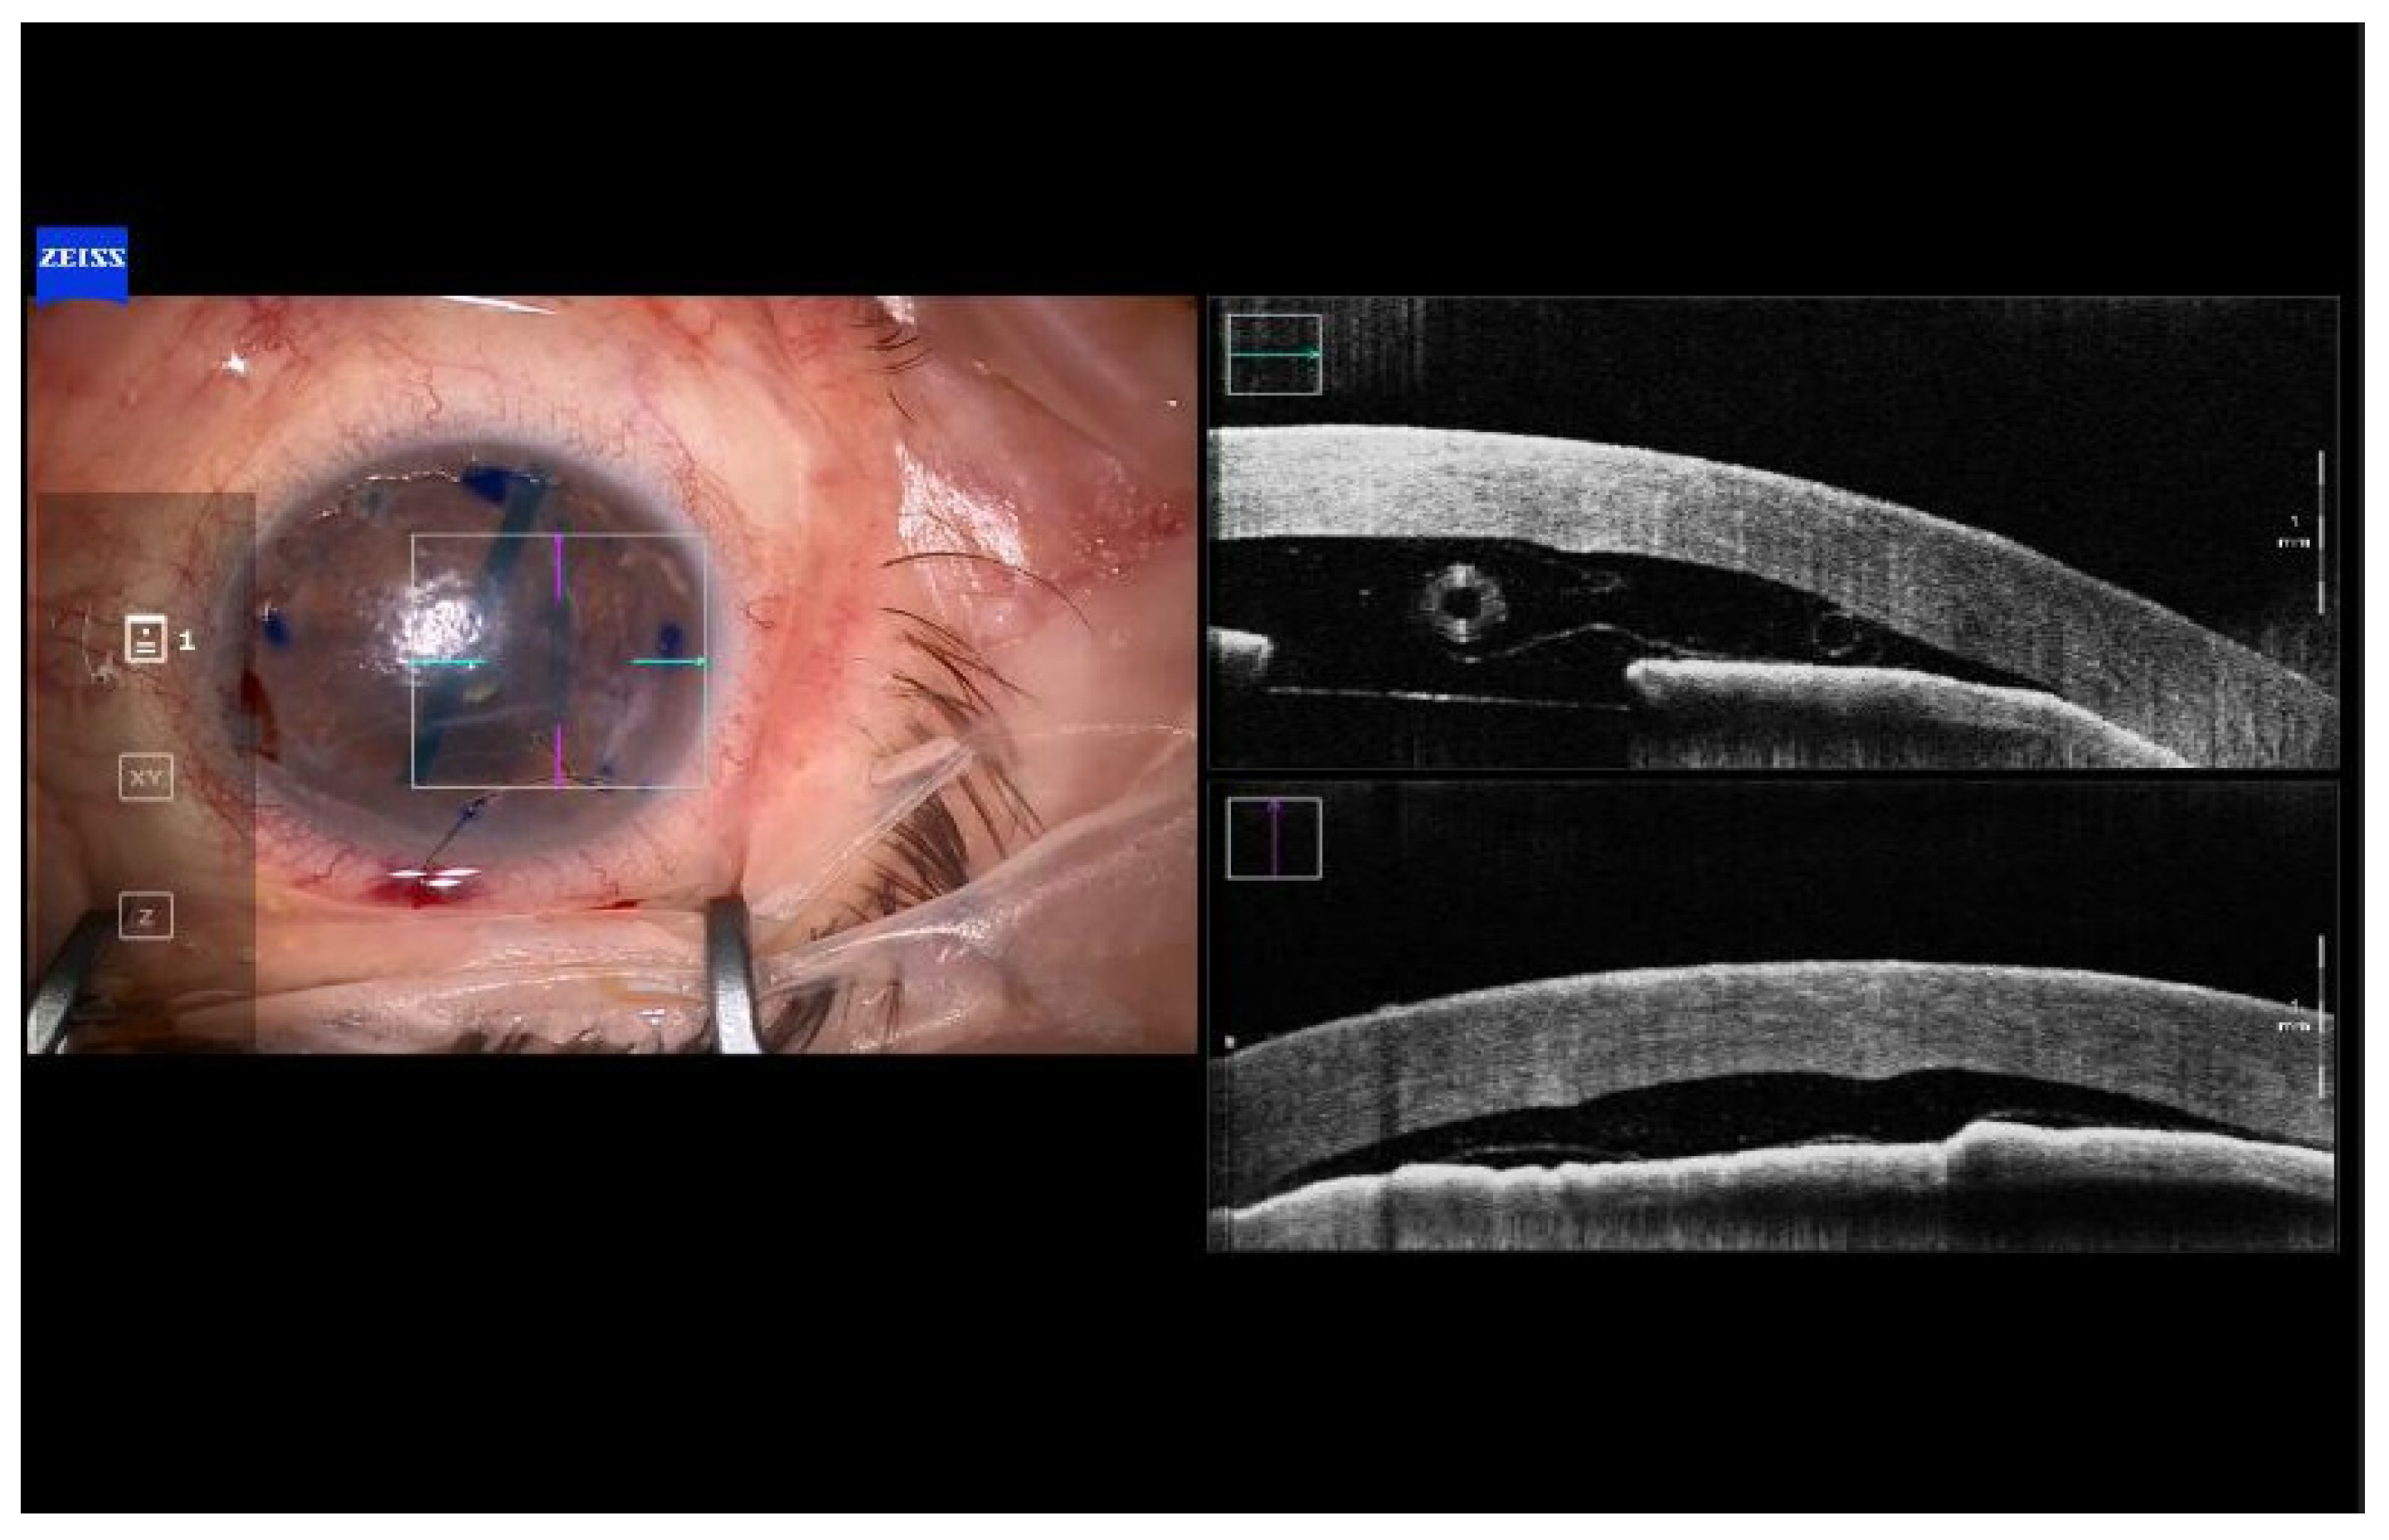

Surgical Technique